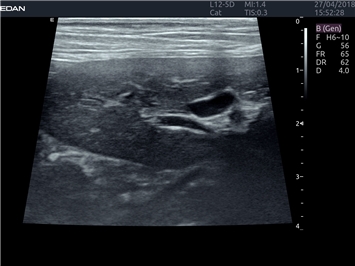

EDAN Acclarix LX4 VET

EDAN Acclarix LX4 VET представляет собой профессиональную ультразвуковую систему, специально разработанную для ветеринарных исследований. Сочетание стабильности, высокой производительности и эффективности делает эту систему идеальным выбором для современной ветеринарной практики.

• Оптимизация изображения для различных видов животных

• Улучшенная детализация структур

• Мультилучевое сложно-составное сканирование (SCI):

• Повышенная четкость изображения

• Улучшенная визуализация сложных анатомических структур